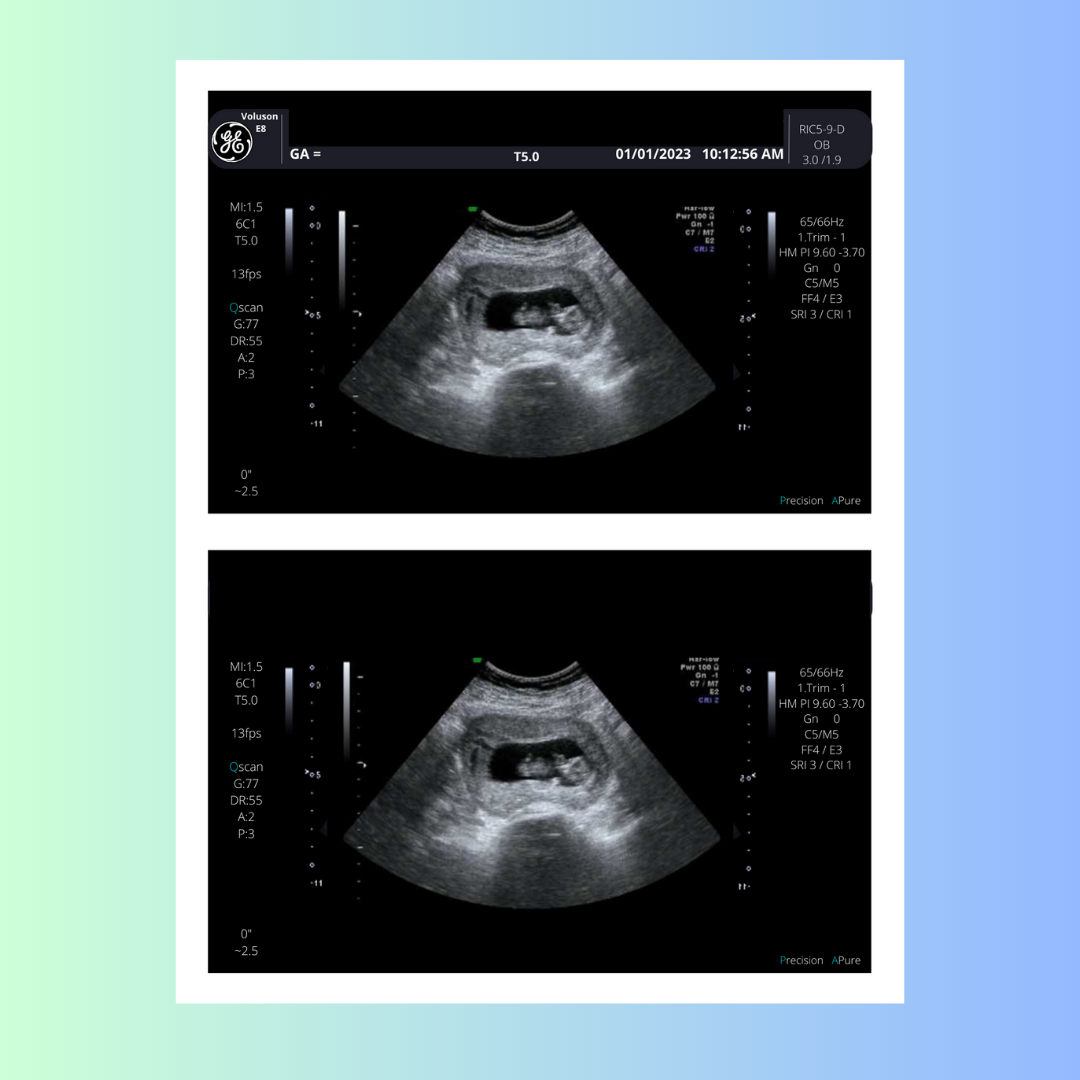

Yes, during your 6-week ultrasound, you should be able to see the gestational sac and the yolk sac. The gestational sac is the early home for your growing baby, and the yolk sac provides essential nutrients until the placenta takes over. While it's still early for detailed images, this ultrasound confirms the progress of your pregnancy.

During your 6-week ultrasound, you should see:

- A small, round gestational sac

- A yolk sac, which appears like a tiny circle near the gestational sac

- A flickering heartbeat, a sign of your baby's developing cardiovascular system